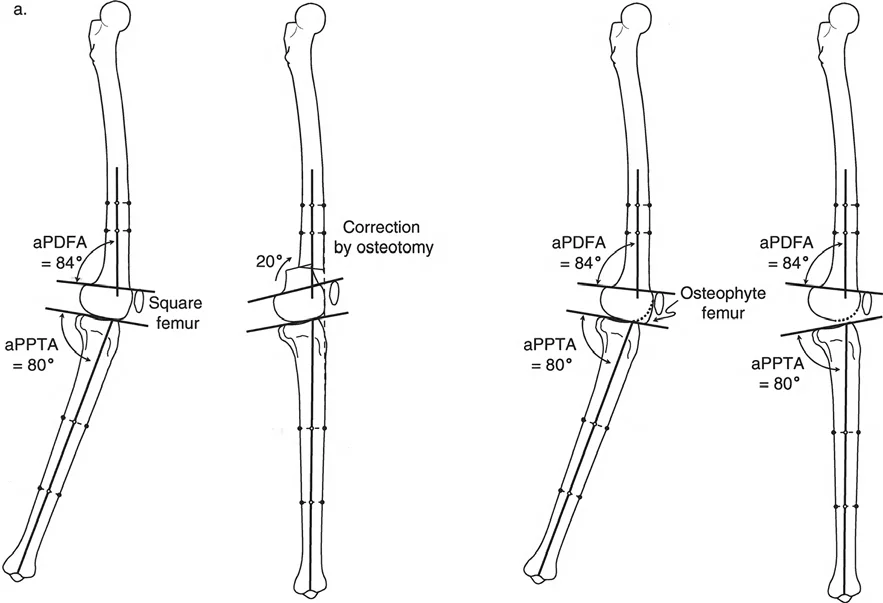

تصحيح تحدد حركة الركبة (Flexion Deformity - FFD)

تحدُّد حركة الركبة هو عدم القدرة على مد الركبة بالكامل. يمكن أن يكون سببه عظميًا أو ناتجًا عن تقلص في الأنسجة الرخوة.

- التشخيص الدقيق: يجب تحديد ما إذا كان تحدد الحركة ناتجًا عن تشوه عظمي (تقوس أمامي في الفخذ أو الساق) أو تقلص في الأنسجة الرخوة (الأوتار الخلفية، محفظة المفصل).

- قطع العظم التمديدي (Extension Osteotomy):

- إذا كان التشوه عظميًا، يتم إجراء قطع عظم تمديدي في عظم الفخذ أو الساق لتصحيح التقوس.

- الأستاذ الدكتور محمد هطيف يؤكد على أهمية عدم تصحيح الساق بأكثر من 90 درجة PPTA لتجنب فقدان الميل الخلفي الطبيعي للساق.

- إزالة النتوءات العظمية (Osteophyte Resection):

- إذا كانت النتوءات العظمية الأمامية تمنع المد الكامل، يمكن إزالتها جراحيًا.